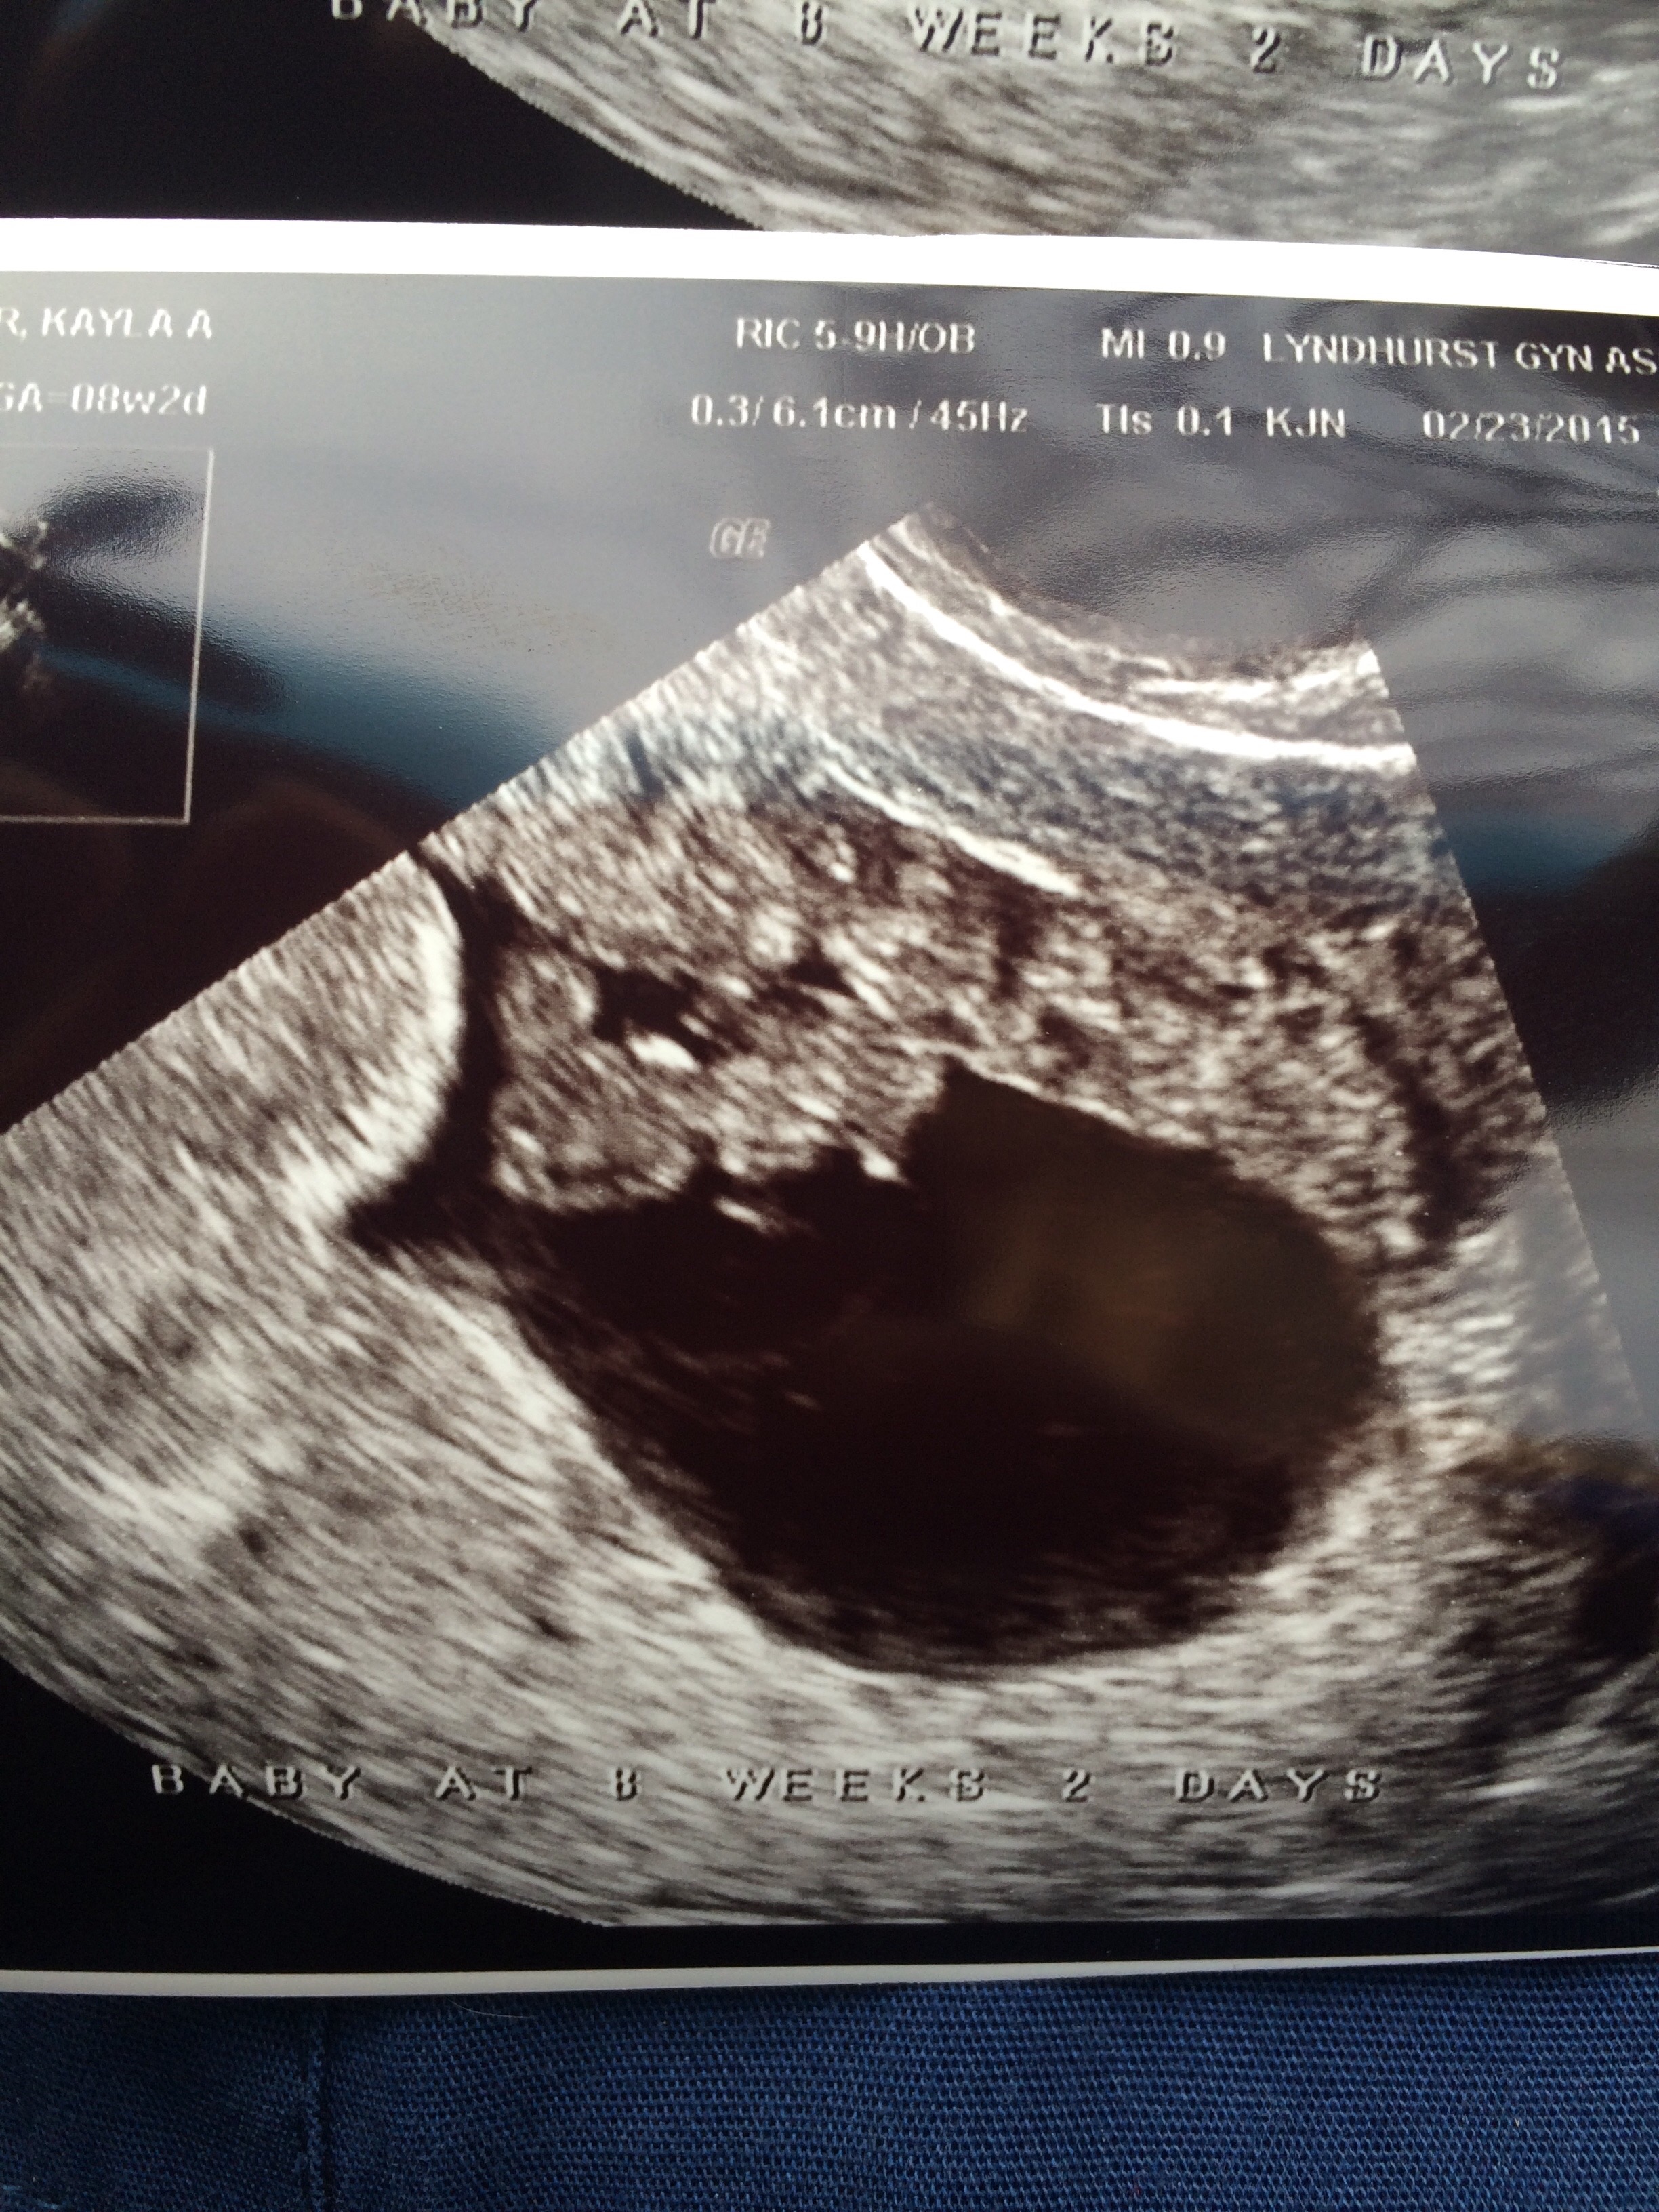

• 8 wk 2 days ❤️